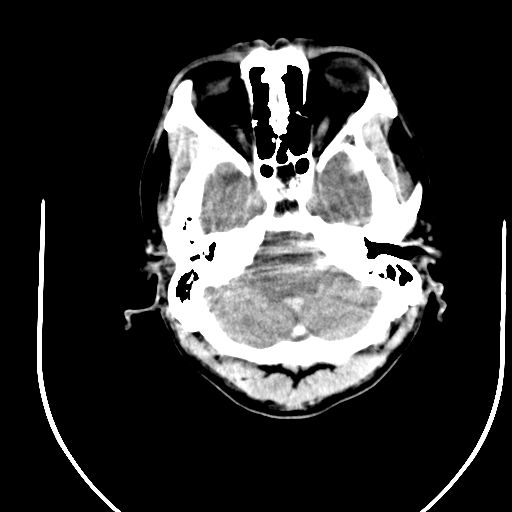

标题: CT24997:M,60Y,突发昏迷30分钟,有高血压病史。

右侧基底节区脑出血并破溃入脑室。

支持楼主诊断,脑中线结构有偏移,脑疝形成可能!

1右侧基底节脑出血伴脑干出血并破入脑室系统脑疝形成2梗阻性脑积水

1)右侧基底节脑出血伴脑干出血并破入脑室系统。2)大脑镰下疝。3)梗阻性脑积水。